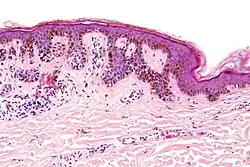

| Micrograph of a dysplastic nevus showing the characteristic rete ridge bridging, shouldering, and lamellar fibrosis. H&E stain. | |

-

Low magnification

Low magnification -

Intermediate magnification

Intermediate magnification -

Very high magnification

Very high magnification